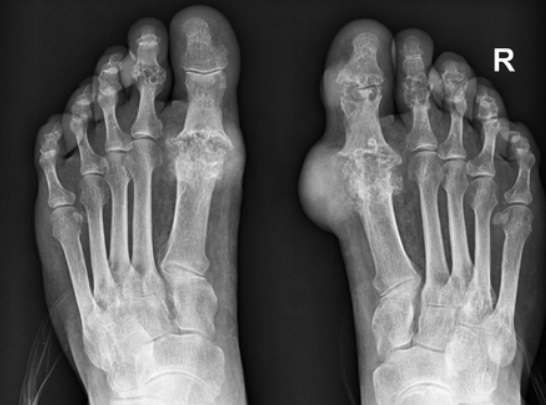

통풍 증상 아홉 번째는 만성 관절염입니다. 통풍이 방치되면 발작성 관절염의 빈도가 점점 잦아지고 침범하는 관절 수도 많아집니다. 회복하는 속도도 더욱 더뎌지고 관절염이 만성으로 발전할 수 있습니다.